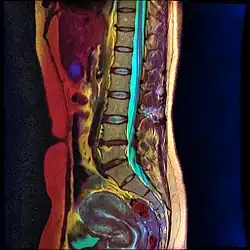

Lumbar sympathetic neurolysis is performed between the L1-L4 vertebrae with separate injections at each vertebra junction. The chemicals used for neurolysis of the nerves cause destructive fibrosis and cause a disruption of the sympathetic ganglia. The vasomotor tone is decreased in the area affected by the neurolysis, which in addition to arteriovenous shunting, create a light pink appearance within the affected area. Lumbar sympathetic neurolysis alters the ischemic rest pain transmission by changing norepinephrine and catecholamine levels or by disturbing afferent fibers. This procedure is mainly used only when other feasible approaches to pain management are unable to be used.[13]

Lumbar sympathetic neurolysis is performed by using absolute alcohol, but other chemicals such as phenol, or other techniques such as radiofrequency or laser ablation have been studied. To aid in the procedure, fluoroscopy or CT guidance is used. Fluoroscopic guidance is the most frequent, giving better real-time monitoring of the needle. The general technique of administering lumbar sympathetic neurolysis involves using three separate needles rather than one because it allows for better longitudinal spread of the chemicals.[13]